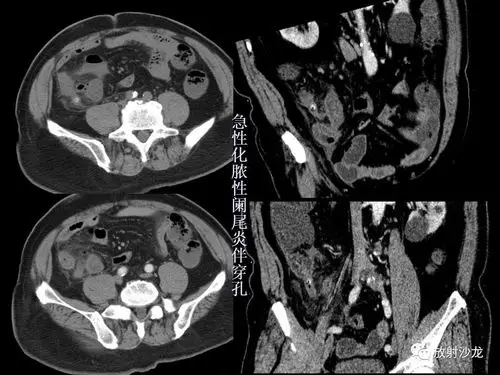

阑尾炎的ct诊断